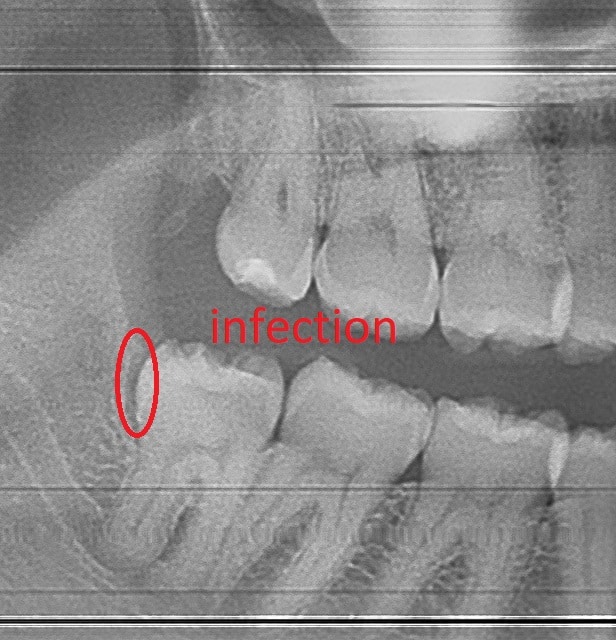

Food impaction caused extensive cavities in the tooth adjacent to the bottom wisdom tooth, requiring a root canal.

Root canal completed because of food impaction

Root canal was completed to get the patient out of pain. Wisdom tooth requires extraction by oral surgeon